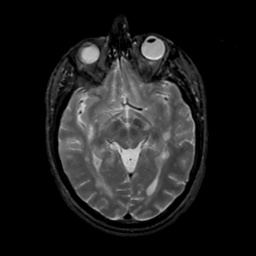

MR Study #13, May 19, 1991 -- Slice #22